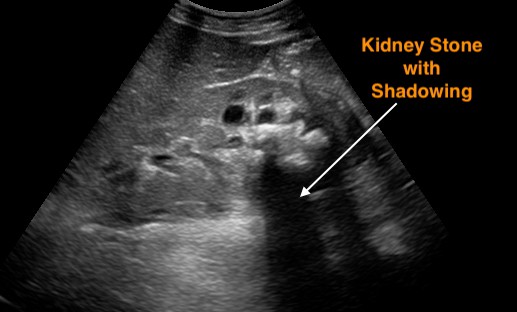

5. kép:

Vesekő ultrahang képe

Ezen a képen vesekövek láthatóak a vese üregrendszerében, melyek hangárnyékot képeznek az epekövekhez hasonlóan.